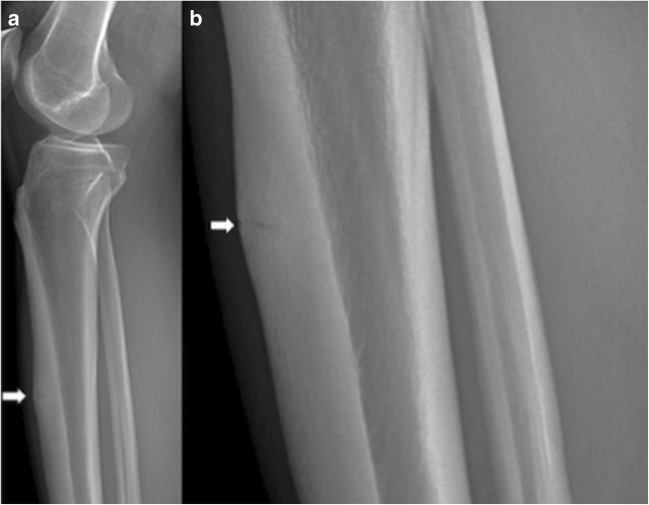

Imaging, though not always necessary, can help confirm the diagnosis. A classic finding on radiographs is the “dreaded black line,” described as a cortical lucency of the mid-anterior cortex of the tibia (Fig. 5a, b) [31]. However, plain radiographs have a low sensitivity (10 to 50%) for detecting stress fractures in the early clinical course. MRI is the imaging modality of choice for diagnosing stress fractures not visible on radiographs, with a sensitivity and specificity of 88 and 99%, respectively [31]. Proton-density and T2-weighted images demonstrate increased signal in the endosteum, reactive soft tissue, and marrow edema with periosteal reaction (Fig. 6) [4, 22, 31, 57].

Fig. 5.

Lateral radiograph of the leg (a) and zoomed area of the lateral radiograph (b) demonstrate horizontal stress fracture within the anterior margin of the tibial diaphysis, with surrounding cortical thickening (arrow) indicative of chronic stress fracture of the anterior margin of the proximal tibial diaphysis.